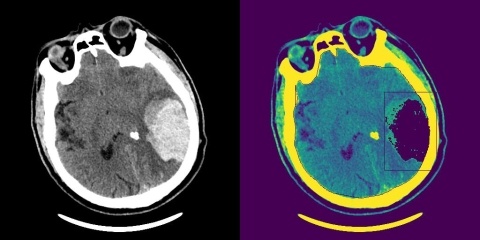

В основе системы уже создан алгоритм анализа МСКТ-снимков. Он позволяет точно определять объём и расположение сложных внутричерепных гематом, а также локализацию повреждений, которые могут угрожать жизни пациента.